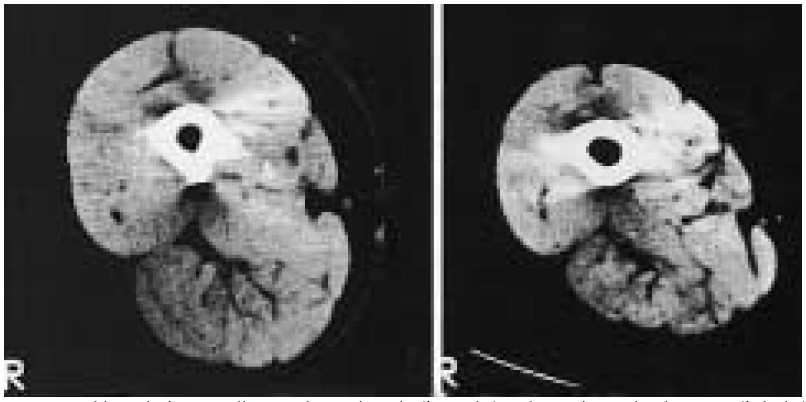

Figure.2 : Tomographie assistée par ordinateur d’un sujet sain (à gauche) et d’un sujet atteint de BPCO (à droite) appartenant au même groupe d’âge. [20]